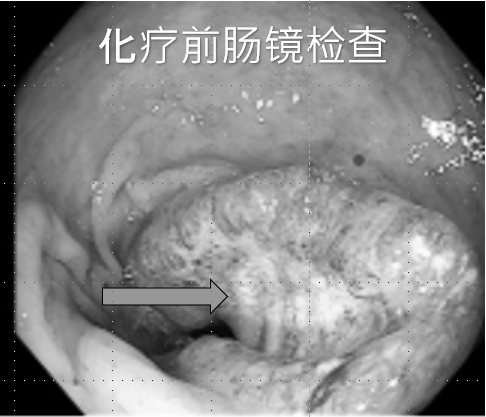

01/

患者秦先生,因“大便带血3月余”诊断“中位直肠中分化腺癌cT4aN1M0 IIIB期”,经多学科MDT讨论,根据NCCN、CSCO指南,予CAPEOX方案新辅助化疗5周期,化疗效果良好,肿瘤 “完全临床缓解(cCR)”。

行腹腔镜直肠癌根治术治疗。

▲术后病理:

●肿瘤位置:瘤床不明显;未见脉管内癌栓及神经侵犯;切缘阴性;未见淋巴结转移;

●TRG评分:0(无肿瘤细胞残留)。病理学完全缓解ypT0N0cM0,患者术后恢复良好。